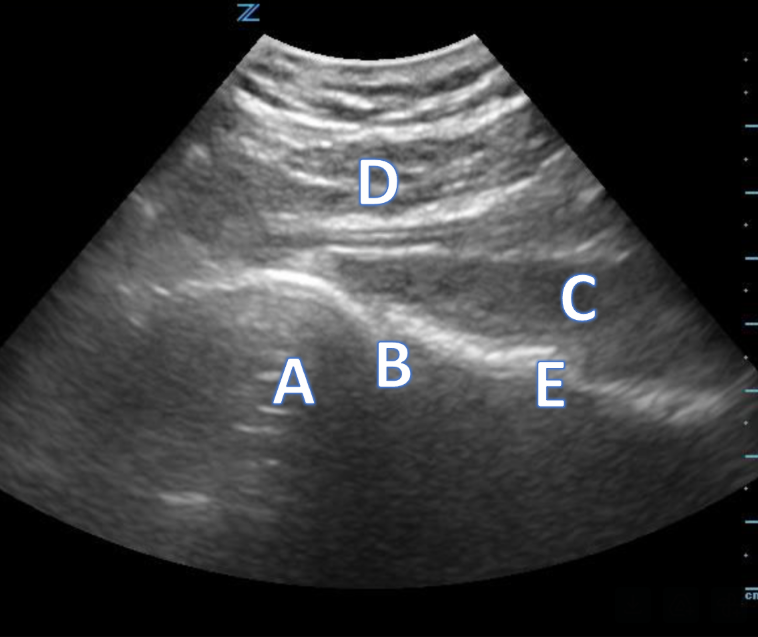

A 21-year-old female presents to the emergency room after falling from dancing on a table and injuring her right ankle. She is in severe pain and unable to bear weight comfortably with swelling and tenderness along the lateral malleolus. X-rays are taken and shown above.